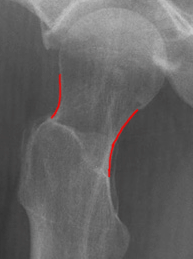

Hüftgelenk a.p.

Cave: selten isoliert, meißt mit Luxation oder Azetabulum# kombiniert), Hüftgelenksluxation

Beurteilungskriterien

- CCD- Winkel (120-130°) Spongiosaarchitektur, Trajektorienverlauf im Schenkelhals (Cave: Bei nicht dislozierten SHF Diskontinuität der Trabekel oft einziges Frakturzeichen!)

- Shenton´sche Linie (Harmonischer Bogen aus kaudaler Schenkelhalskontur und der kranialen Zirkumferenz des For. obturatum)

- Gelenkstellung, Gelenkspaltweite (4-5mm nach medial, 3-4mm nach kranial), Luxation => Hüftkopf in ap und axialer Aufnahme in Azetabulum zentriert? Hüftkopfrundung?

- Azetabulumfraktur: vorderer und hinterer Pfannenrand, Pfannendachkontur, Köhlersche Tränenfigur, ggf. Zusatzaufnahmen (Ala- und Obturatoraufnahme), sowie CT

- medialer Azetabulumdachbogen (45° von der Hüftkopfmitte ausgehend nach vorne (!); Teil der lasttragenden Zone des Azetabulums, vgl. Obturatoraufnahme)

- Trochanter major et minor (Abriss, pertrochantäre #?)

- Weichteilzeichen (Fettstreifen medial des M.gluteus minimus zw. M.glutaeus minimus und medius, medial des M.iliopsoas; Konturschatten des M.obturatorius int.)